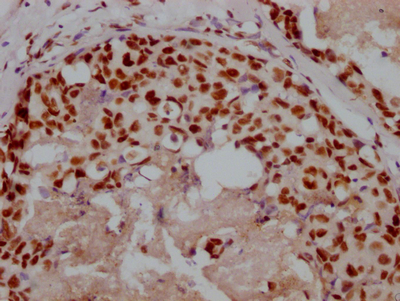

Immunohistochemistry of paraffin-embedded human pancreatic tissue using CSB-PA064019ESR2HU at dilution of 1:100